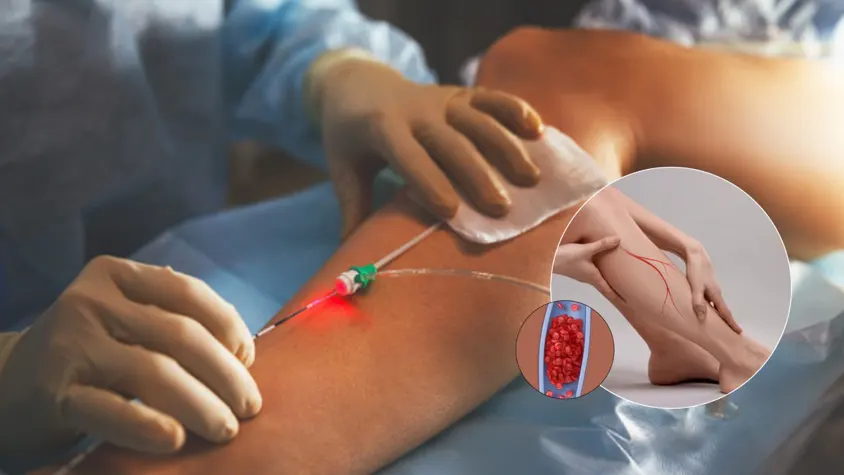

Endovenous Ablation (Radiofrequency)

- A thin catheter is inserted into the diseased vein through a small needle stick

- Heat energy seals the vein shut from the inside

- Blood reroutes naturally to healthy veins

- Performed in 30 mins; you walk immediately afterward

- Excellent success rate for treating great or small saphenous veins